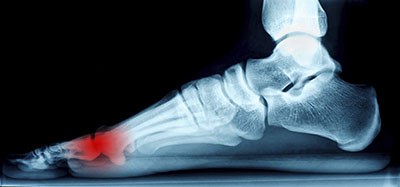

A neuroma is thickened nerve tissue. Morton’s neuroma (also known as an intermetatarsal neuroma) is the most common one that affects the foot. It occurs between your third and fourth toes between the metatarsal bones. You can also get neuromas in other parts of your foot.

The tissue thickening and enlargement that causes a neuroma is due to compression and irritation of the nerve. Untreated neuromas can result in permanent nerve damage and chronic pain.